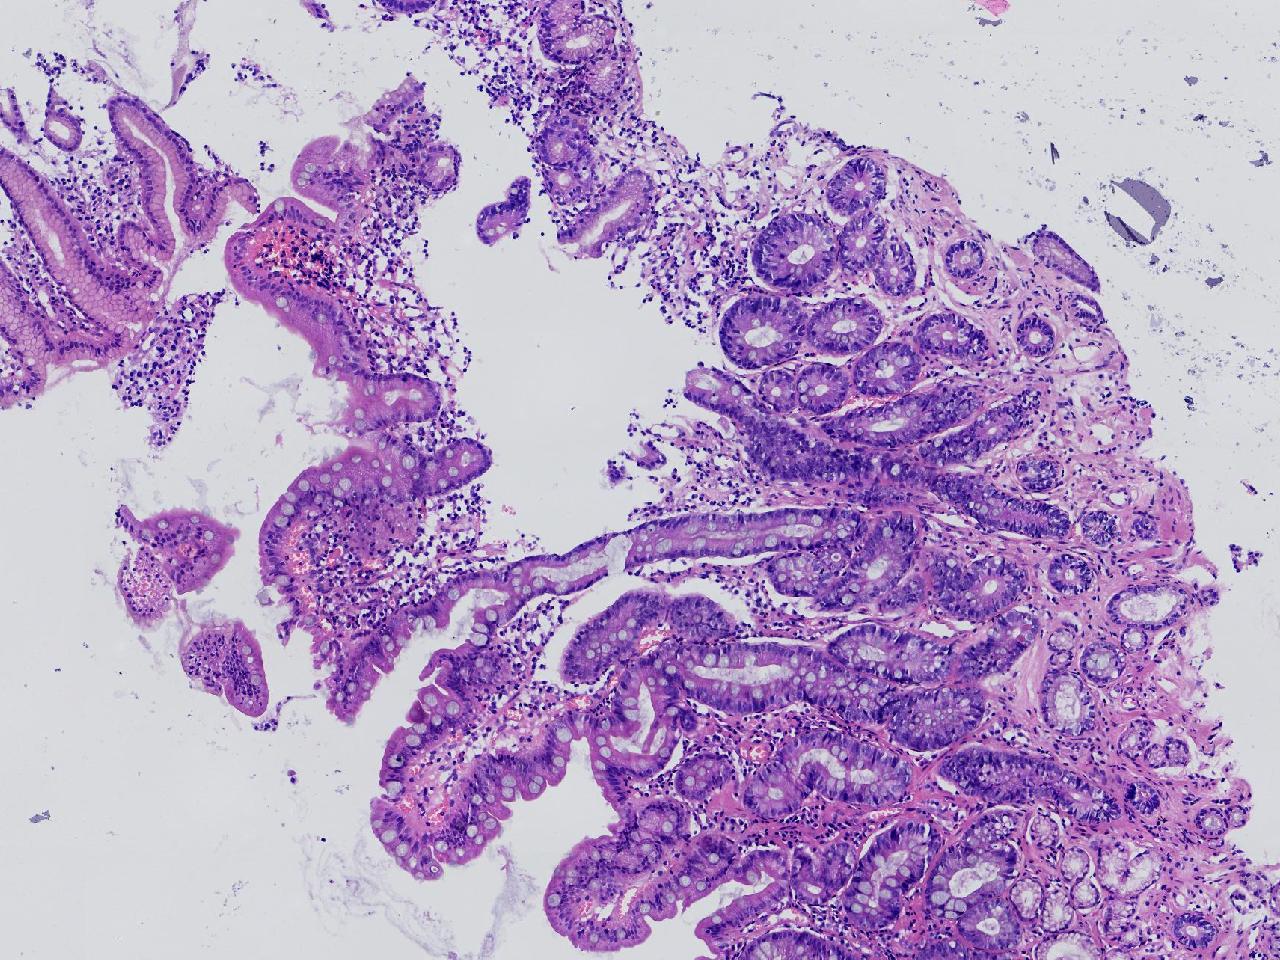

1.间质内淋巴组织有问题吗? 2.有没有低瘤变?

一般病史男,65岁,胃镜活检,胃窦粘膜红白相间,花斑样改变,大弯侧粘膜变薄,血管透见,可见多发片状充血糜烂灶及点状褐色物覆着,活检2块送检,质软弹性可。

标本名称胃窦活检

大体所见灰白色不整形软组织2块,直径均0.2厘米。

慢性萎缩性胃炎伴肠化,固有层淋巴细胞聚集

萎缩性炎,伴有肠化,淋巴组织挤压变形,感觉没有太大的问题。

炎性,无瘤变。